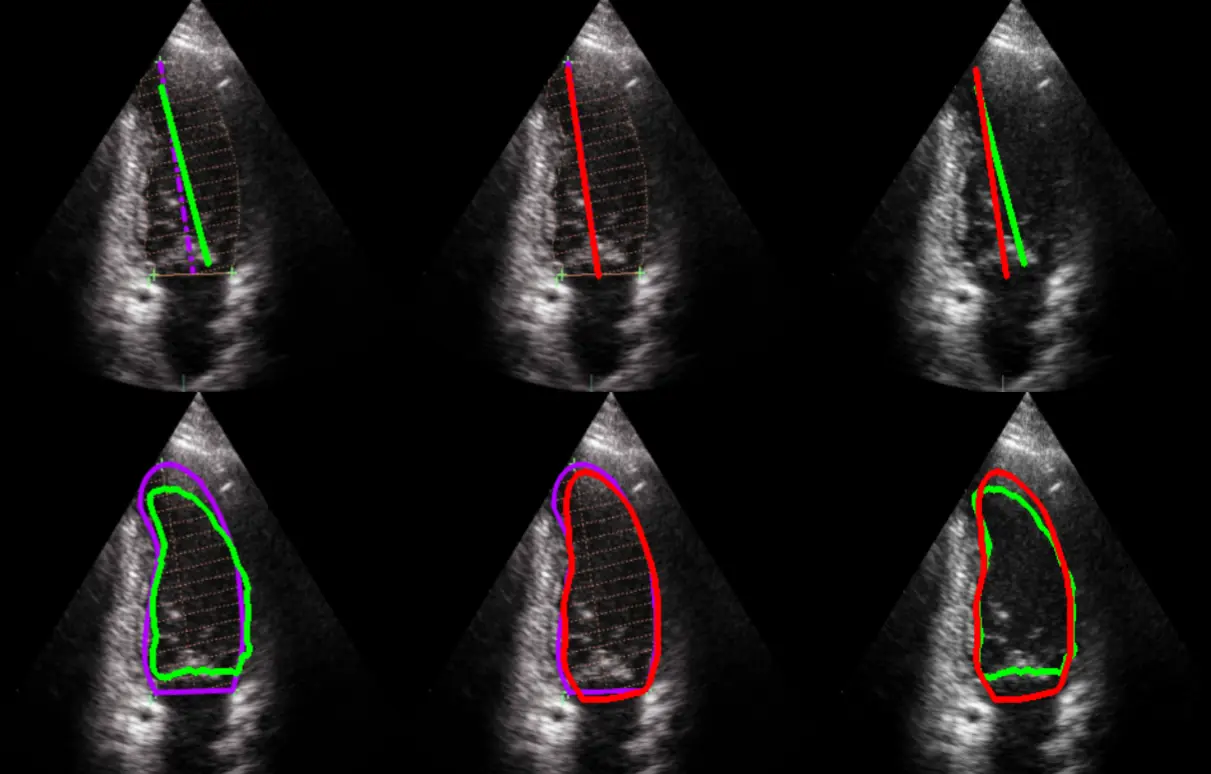

- Riconoscimento della posizione delle valvole cardiache su immagini ecografiche o TC

- Calcolo delle dimensioni minime e massime del cuore, utile per la valutazione morfologica

- Integrazione dei moduli AI: forniamo componenti software per il riconoscimento e la segmentazione automatica.

- Ottimizzazione per imaging medicale: i modelli sono calibrati su immagini TC, RM, ecografiche ed endoscopiche.

- Modelli di deep learning per segmentazione e classificazione

- Algoritmi di ricostruzione volumetrica e analisi morfologica